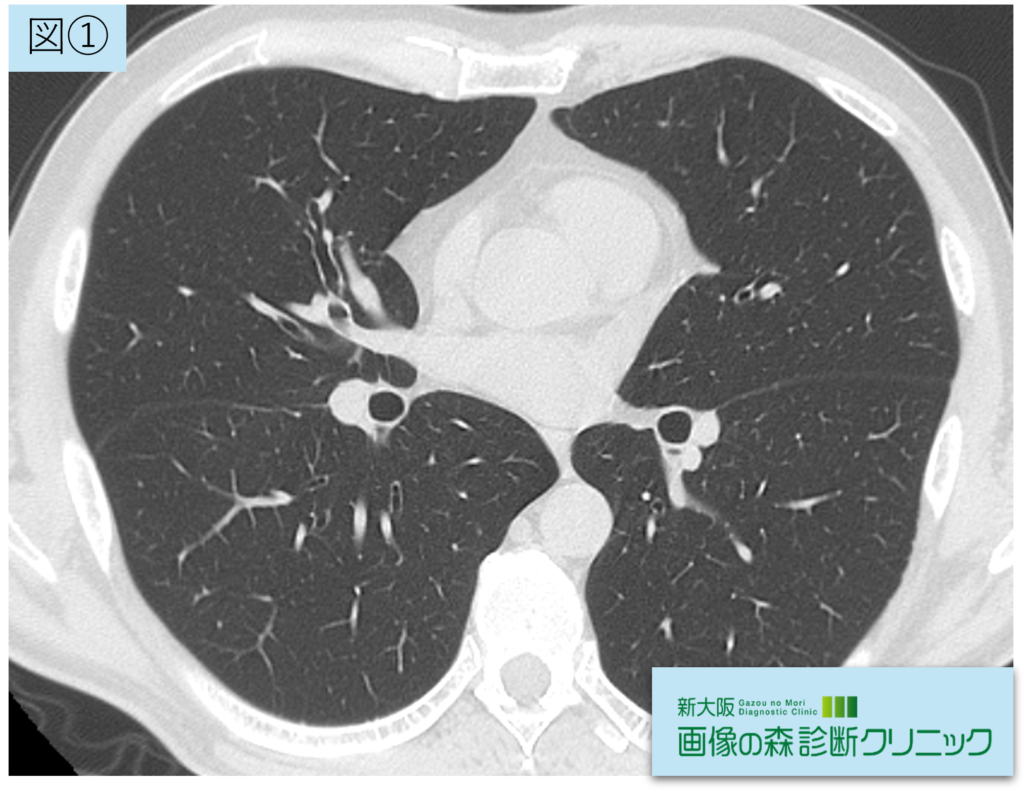

正常画像(横断像)

図①:正常画像